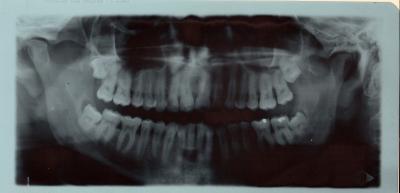

Da ist die Weisheit

Am kommenden Dienstag habe ich den Vorbesprechungstermin. Mindestens einer, von vier, könnte laut Zahnarzt ein Problem darstellen. Mal sehen, was der Fachmann sagt. Er hat nen guten Ruf, kenne ihn als Kunden der Tanke. Da macht er auch einen netten Eindruck auf mich.

Mein Ziel ist es, alle 4 auf einen Streich ziehen zu lassen. Und ich bete um ne Vollnarkose. Ich bin fürs Heldentum nicht geschaffen.